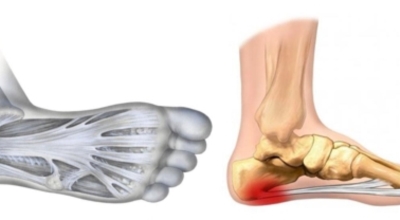

족저 근막이란 발가락 시작지점부터 발뒤꿈치뼈까지 발바닥 전체를 감싸고 있는 두꺼운 막입니다. 족저 근막은 발바닥 아치를 유지해 발바닥이 지면을 내딛음으로써 발생하는 충격을 흡수하는 중요한 역할을 수행하는데요 이 족저 근막에 일차적으로 서서히 조직 손상이 일어나고 계속적인 활동으로 인해 염증이 커지면서 발 뒤꿈치 부근 통증을 일으키게 되는데요 염증은 무리하고 반복적인 동작, 과도한 사용으로 마찰에 의해 발생합니다.

족저 근막염 증상은 보통 서서히 발생하며, 특징적으로 환자는 아침에 일어난 직후 처음 몇 발자국을 걸을 때 심한 통증을 호소합니다. 아침에 일어나서 첫 걸음을 걸을 때 수면 중 이완되지 않아 있던 족저 근막이 쫙 펴지면서 극심한 통증을 느끼게 된다고 하는데요 또한 장시간 걷거나 계속 서 있어도 통증이 증가되고, 체중이 실리면 통증이 더욱더 심해지는 게 일반적입니다. 발꿈치 안쪽을 눌러보면 묵직한 통증이 있는 것이 특징이라고 할 수 있습니다.